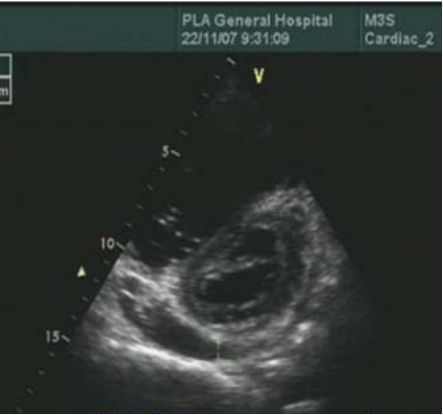

超声心动图

右心衰:右室大,左室小,左室呈D形,少量心包积液

Rudski LG, et al. J Am Soc Echocardiogr 2010;23:685–71